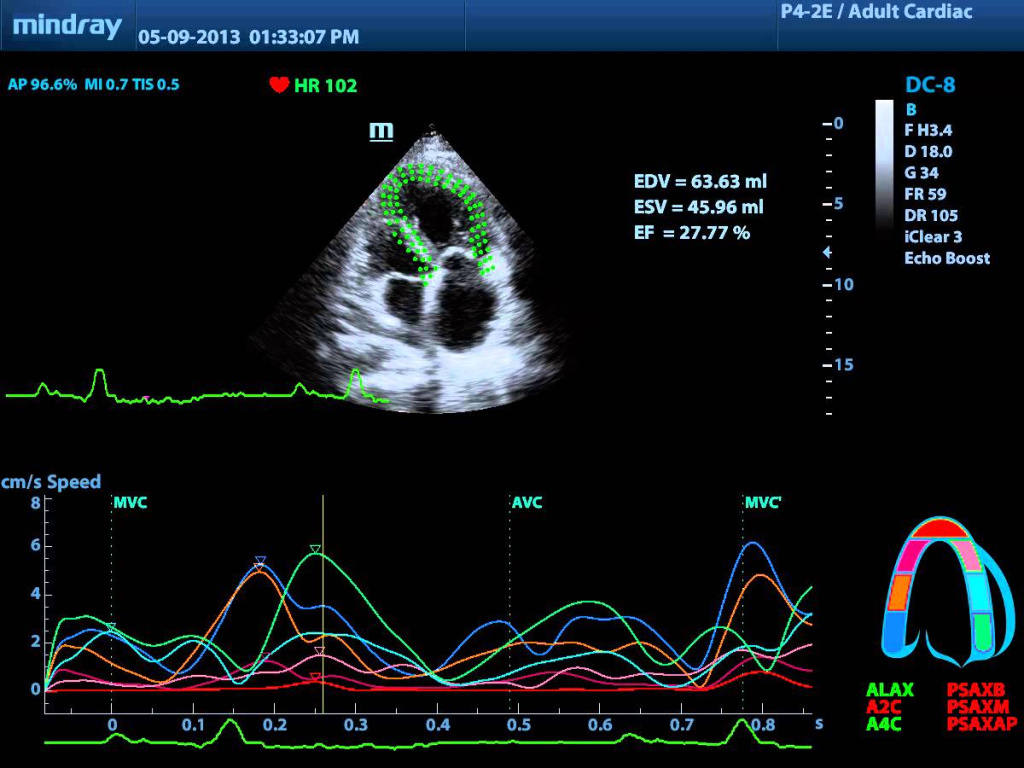

Ниже представлено изображение, полученное с помощью прибора Mindray DC-8 в режиме Tissue Tracking.

Ниже представлено изображение, полученное с помощью прибора Mindray DC-8 в режиме Tissue Tracking и выводам Velocity vector на экран прибора.